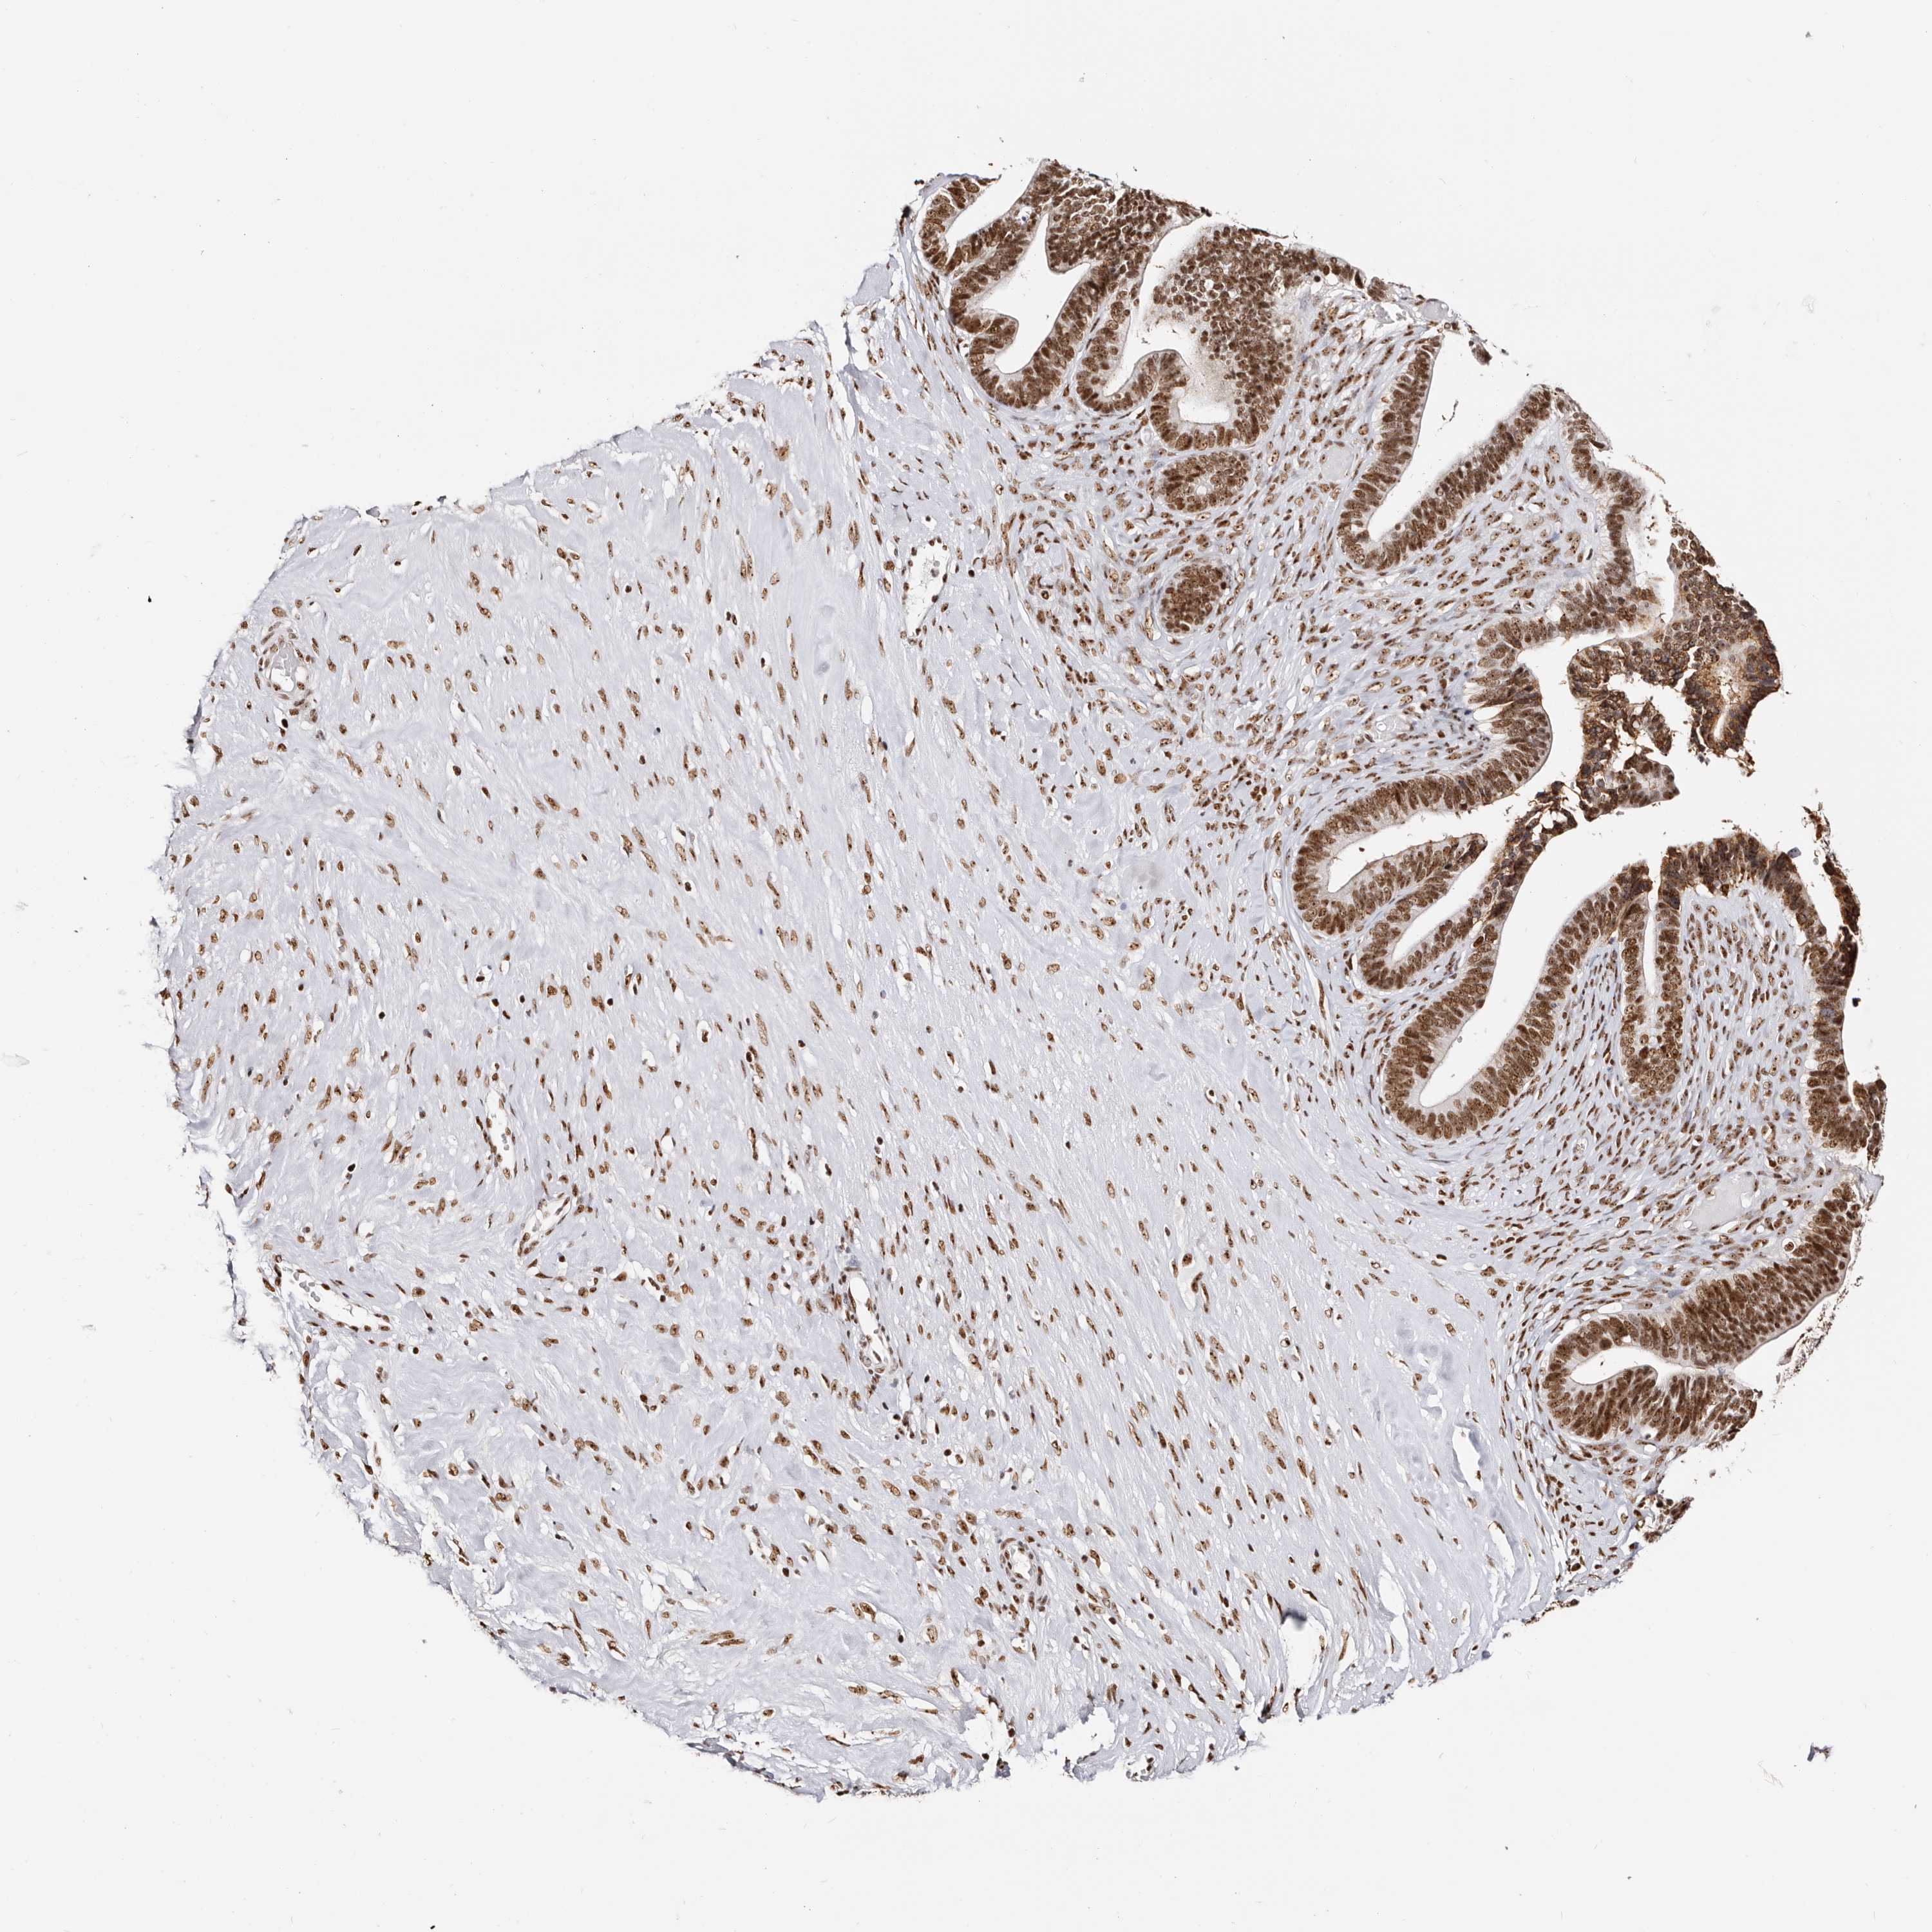

OVARIAN CANCER - Protein expressioni

A mouse-over function shows sample information and annotation data. Click on an image to view it in a full screen mode. Samples can be filtered based on level of antibody staining by selecting one or several of the following categories: high, medium, low and not detected. The assay and annotation is described here.

Note that samples used for immunohistochemistry by the Human Protein Atlas do not correspond to samples in the TCGA dataset.

Antibody stainingi

Antibody staining in the annotated cell types in the current human tissue is reported as not detected, low, medium, or high, based on conventional immunohistochemistry profiling in selected tissues. This score is based on the combination of the staining intensity and fraction of stained cells.

Each image is clickable and will lead to virtual microscopy that enables deeper exploration of all samples and also displays staining intensity scores, fraction scores and subcellular localization as well as patient and tissue information for each sample.

Antibody HPA030142

Antibody HPA030143

Cystadenocarcinoma, serous, NOS

Carcinoma, endometroid

Cystadenocarcinoma, mucinous, NOS

Carcinoma, NOS